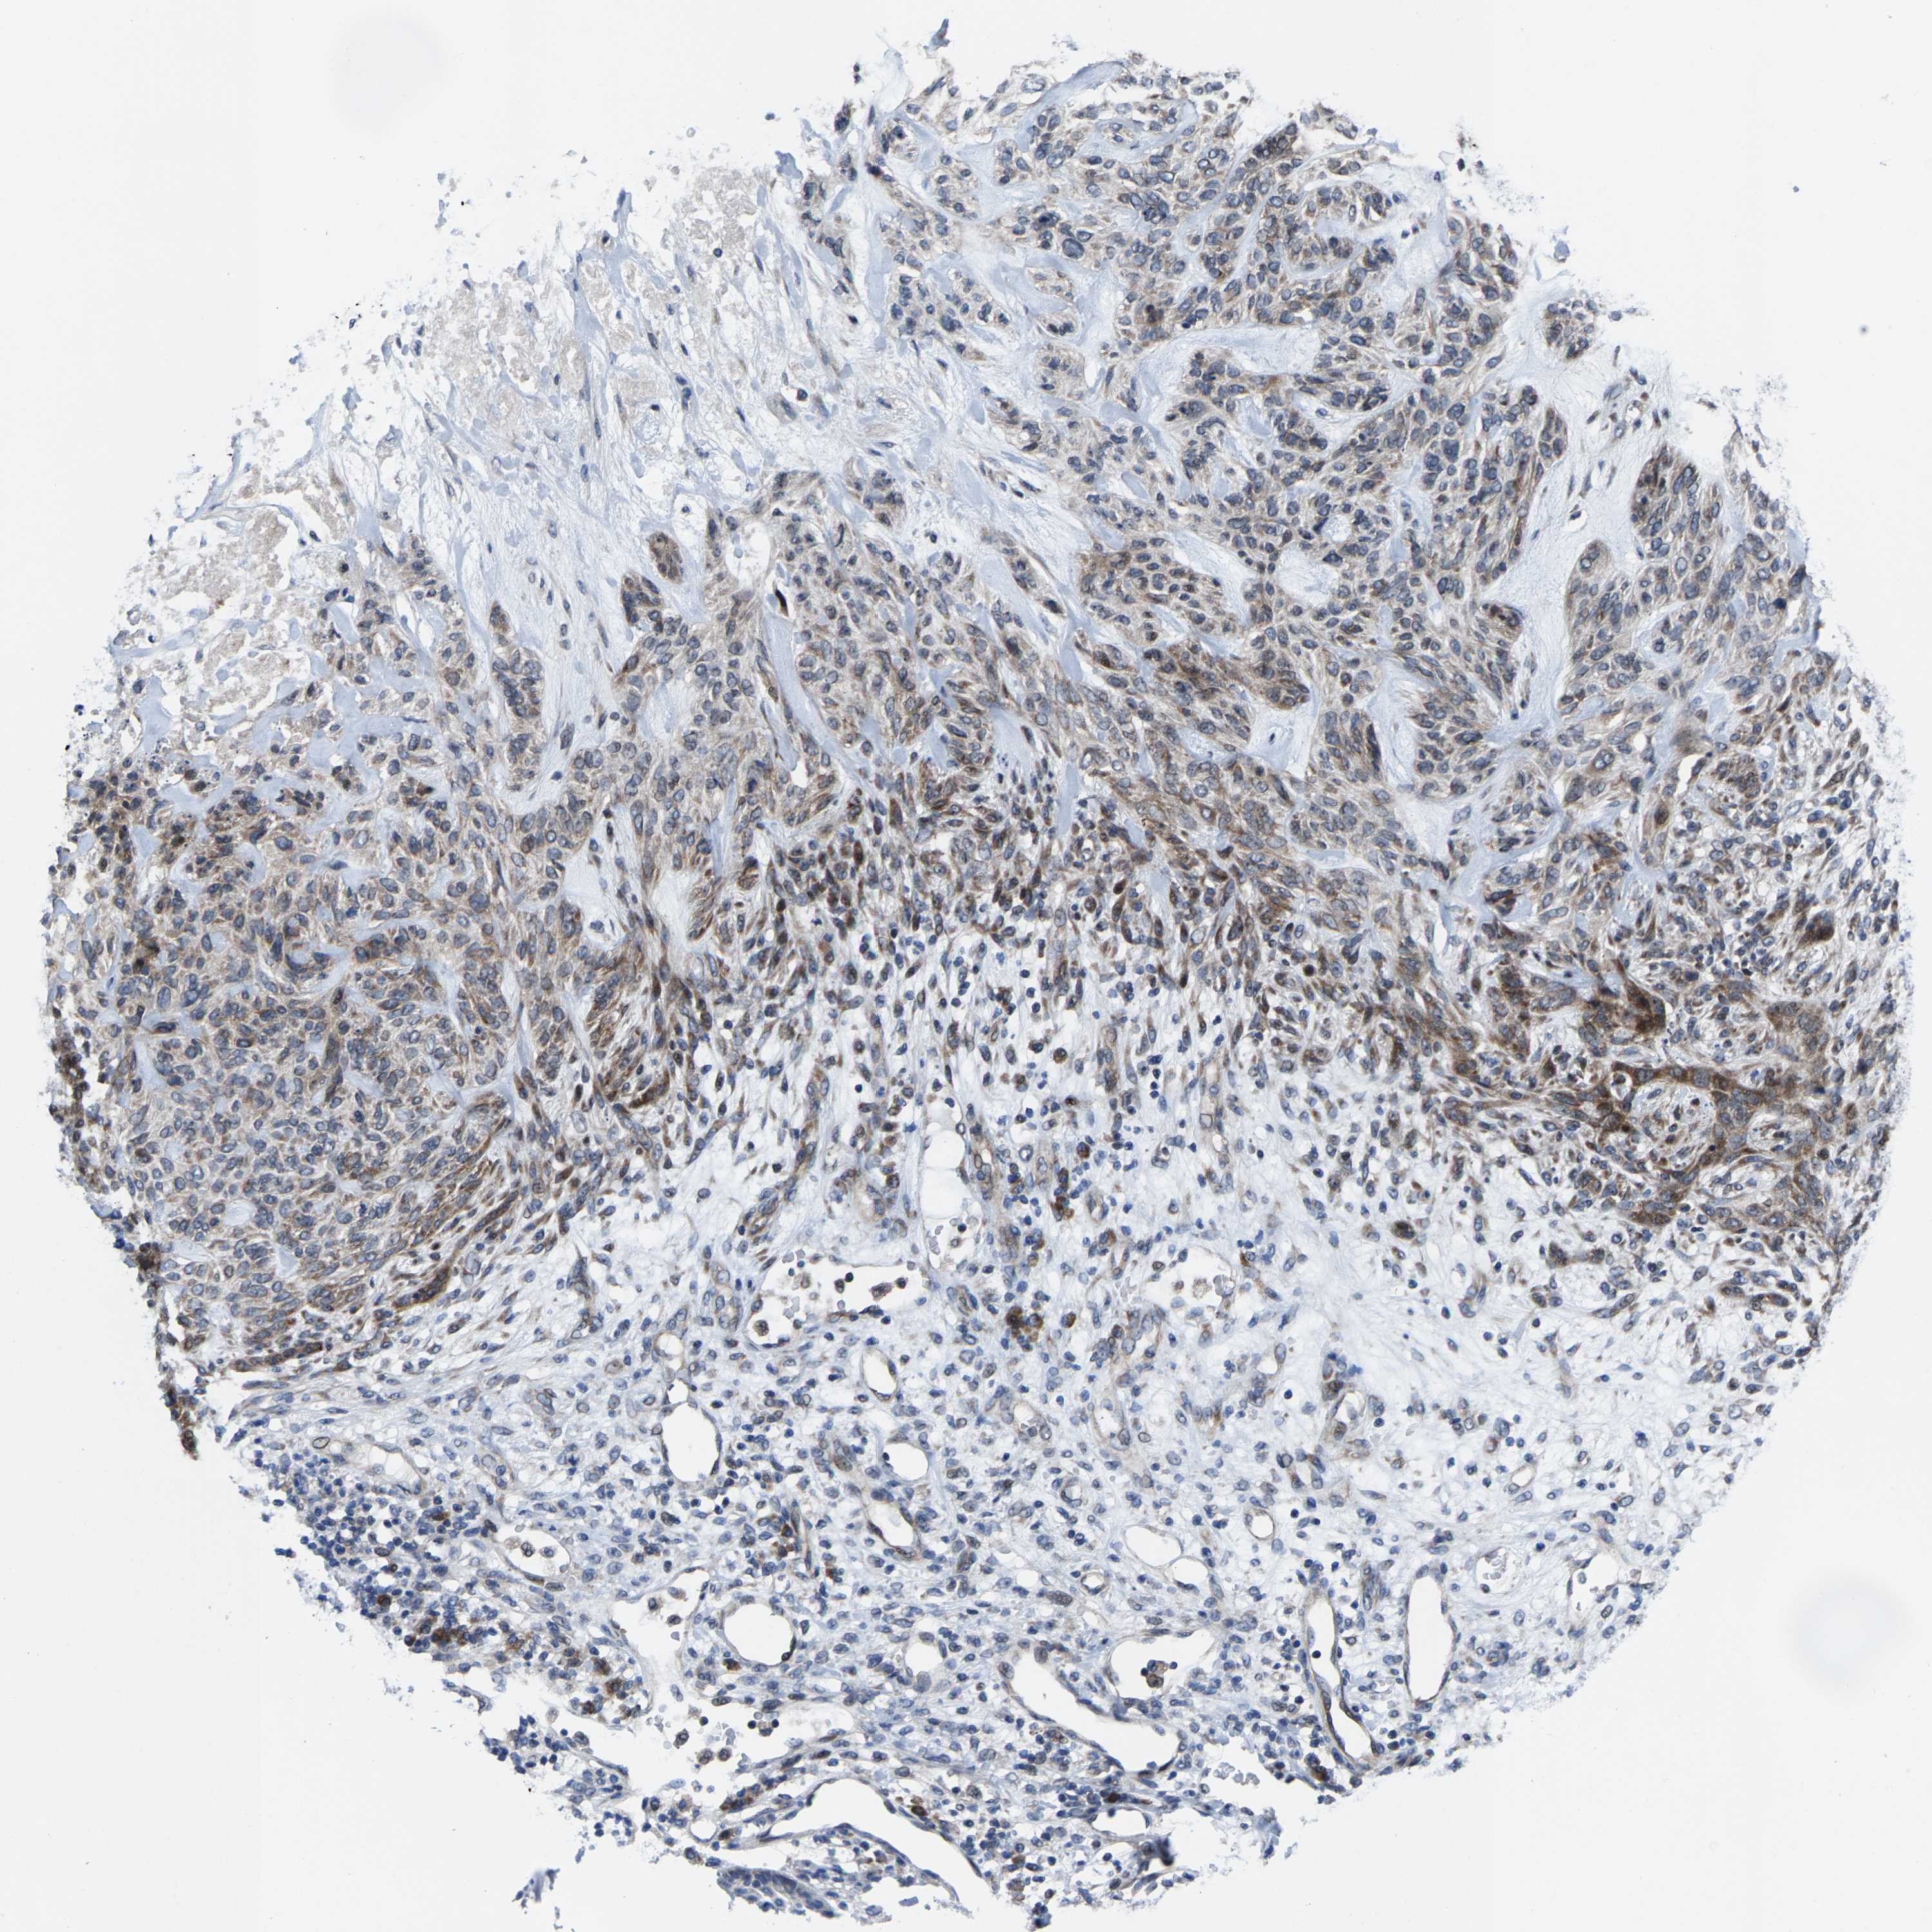

CANCER SKIN CANCER Show tissue menu

Basal cell and squamous cell cancer

SKIN CANCER - Protein expressioni

A mouse-over function shows sample information and annotation data. Click on an image to view it in a full screen mode. Samples can be filtered based on level of antibody staining by selecting one or several of the following categories: high, medium, low and not detected. The assay and annotation is described here.

Antibody HPA020960

Antibody HPA020965

Staining

High

Medium

Low

Not detected

Intensity

Strong

Moderate

Weak

Negative

Quantity

>75%

75%-25%

<25%

None

Location

Nuclear

Cytoplasmic/membranous

Cytoplasmic/membranous,nuclear

Basal cell carcinoma

Squamous cell carcinoma, NOS

Squamous cell carcinoma, metastatic, NOS